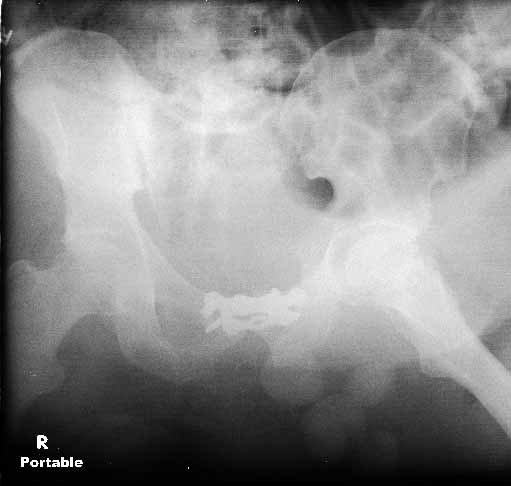

Five dayslater we was doing much better and was deemed fit for surgery. The site of his SP tube had completely healed up without evidence of infection. We took him to the OR to plate his symphysis, making our Pfannenstiel incision low to avoid the SP site. During plating we notice at one point some murky fluid in a little pocket deep inside his pelvis. The was sent for gram stain and culture and came back GPC and ultimately grew out enterococcus. We completed the symphseal plating & packed the wound with antibiotic beads. We brought him back at 48 hours for repeat I&D and removal of the beads and closure. He tolerated both of these surgeries well. About 5 days later(roughly 2 1/2weeks afterhis injury)his wound in the front was looking good and there was no evidence for infection. So he was brought back to the OR for posterior pelvic fixation. My plan had been to do an ORIF and place SI screws, but I couldn't get adequate inlet or lateral views. So we did an open reduction and posterior transiliac plating. The reductions in the front and the backwere difficult due to both his size and due to the time that had elapsed since his injury.I've enclosed pre and post xrays.

The patient is a 63 yo man who was crushed at work 5 days ago and sustained an unstable pelvic fracture with a GU disruption. I have assumed his care today. I am told he has an extraperitoneal bladder rupture but based on the cysto I am concerned about a urethral disruption. He does not otherwise have any significant injuries or medical problems, but he is severely obese (350 lbs+). Xrays and CT cuts are enclosed.